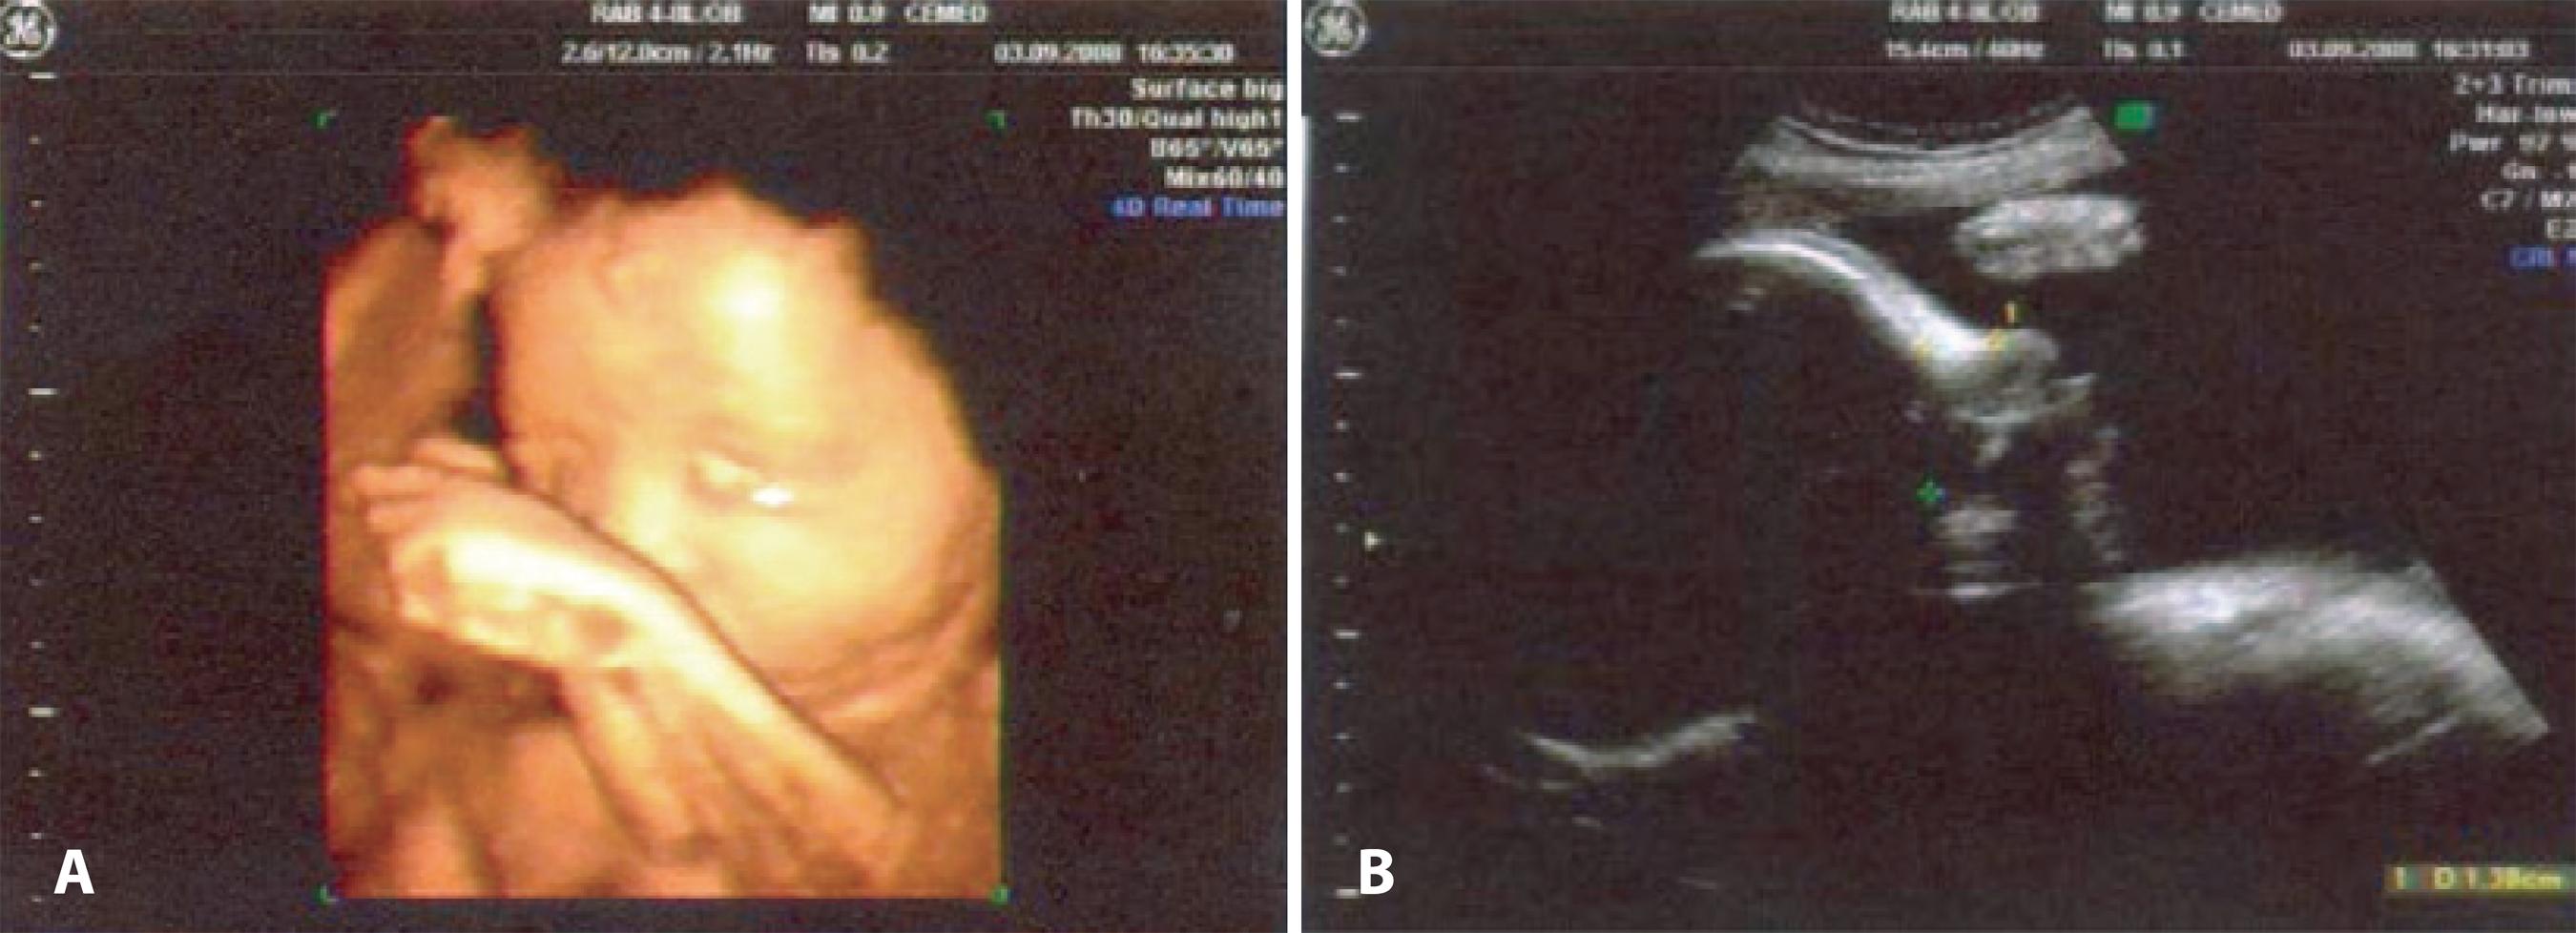

CAL, an 11-day-old, white female, had a bluish mass of cystic firm consistency below the medial canthal tendon on her left side. A fetal morphological ultrasound scan (2- to 4-MHz transducers) performed at 40 weeks of pregnancy showed a discreet bilateral cystic swelling on the epicanthus (Figures 1 A and B).

Figure 1 Intrauterine ultrasonography of a 40-week-old fetus. A) Three-dimensional reconstruction ultrasonography (2-MHz linear transducer), where a swelling can be seen in the region of the left eye epicanthus (white arrow). B) The cephalic frontal seccional image (4-MHz linear transducer) shows a cyst formation with hypoechogenic content (cross mark) that is consistent with dacryocystocele.